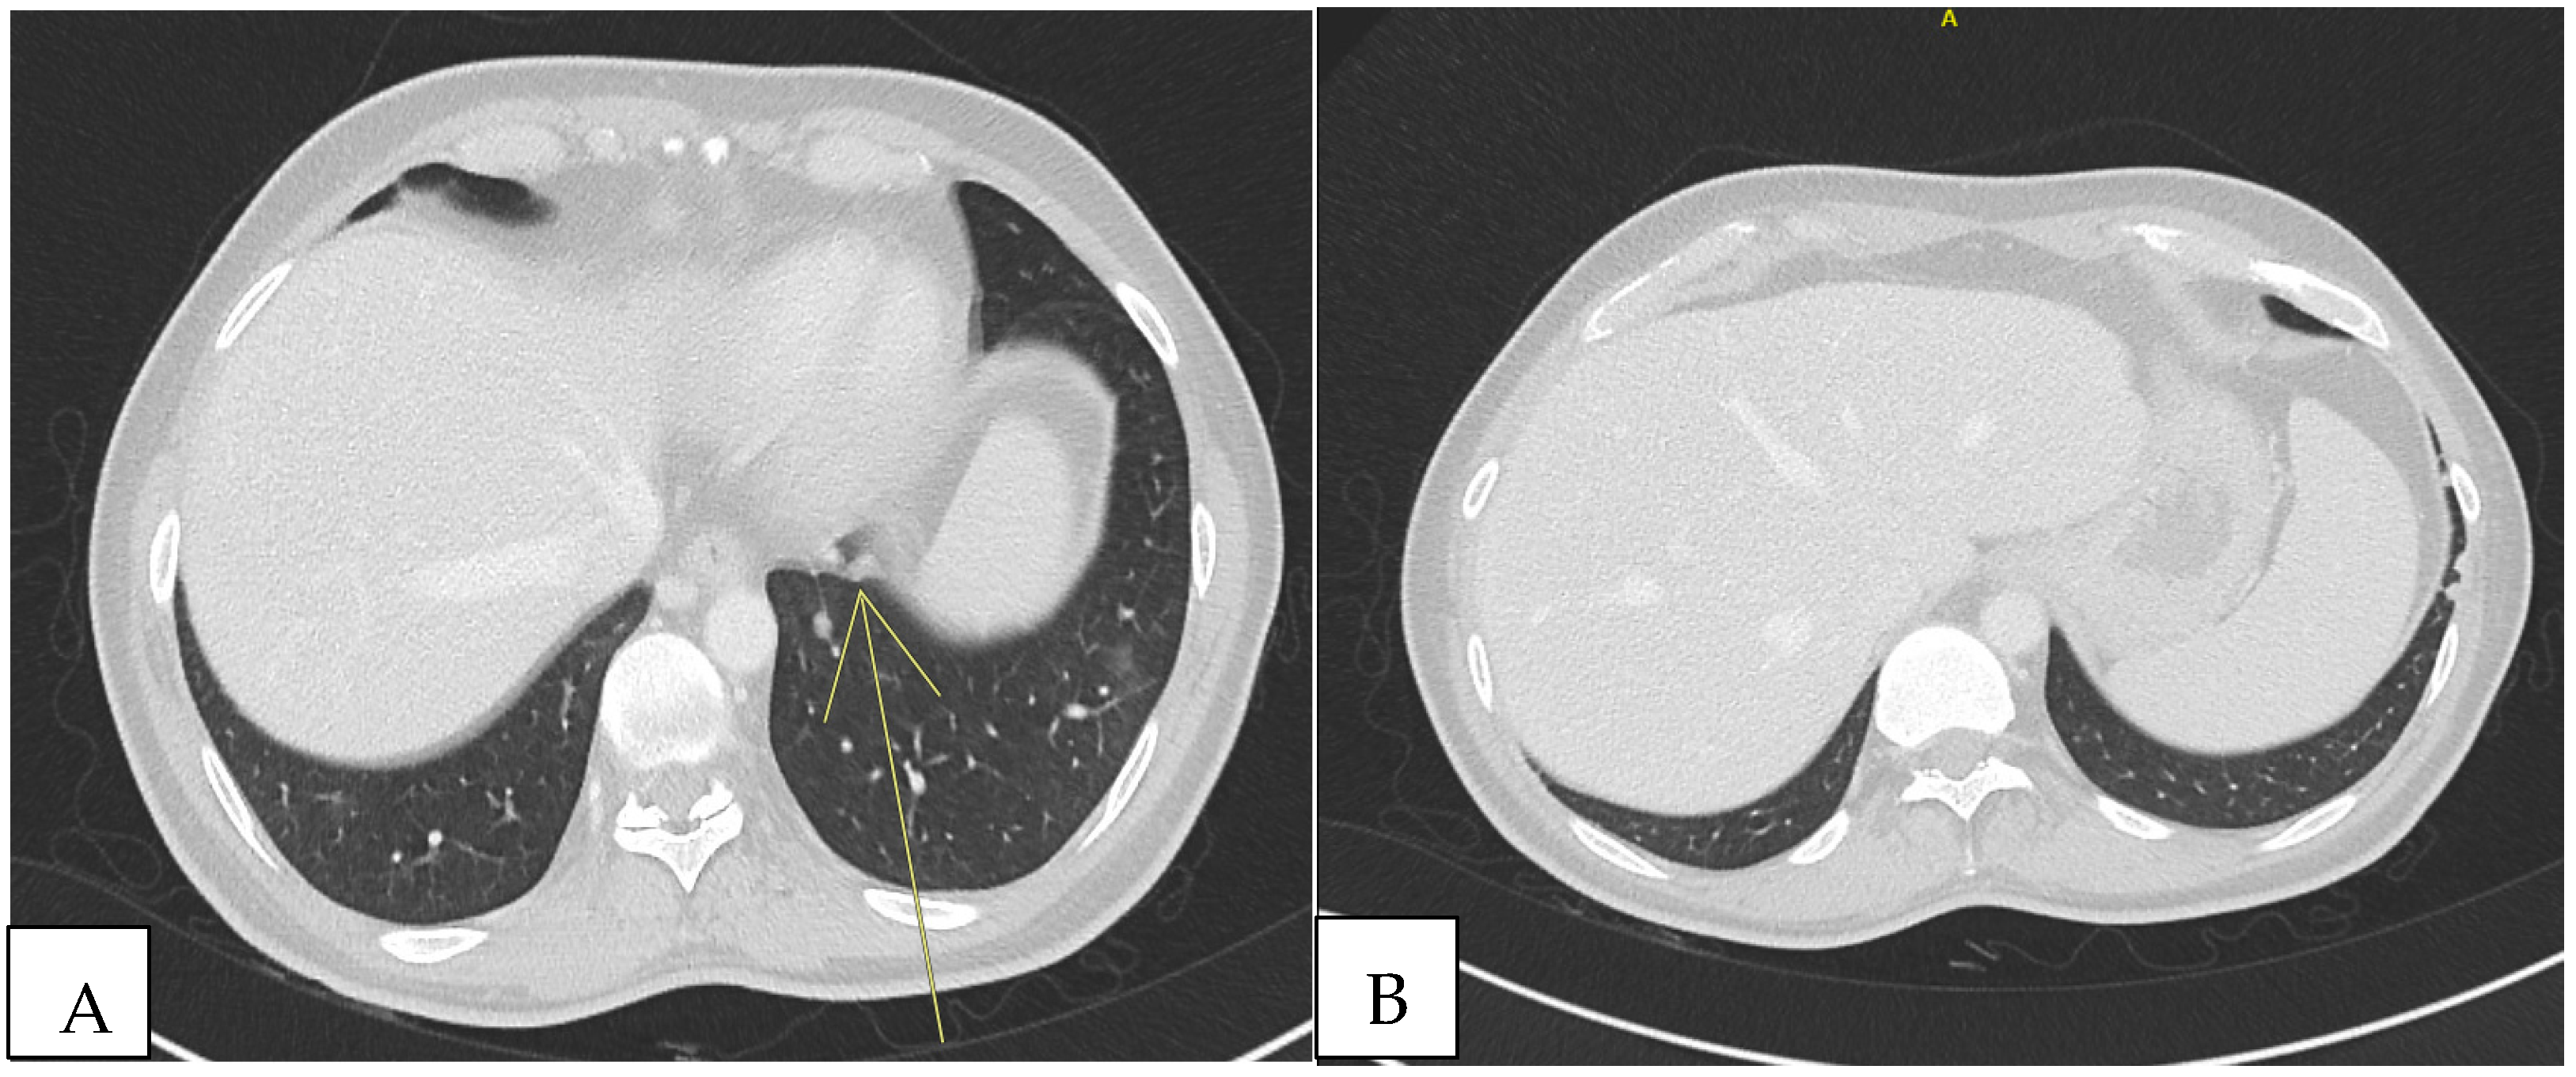

Because of the positive Murphy’s sign, he underwent abdominal ultrasound, which detected hepatomegaly without focal lesions. A total-body computed tomography (CT) scan revealed multiple supra- and infra-diaphragmatic lymphadenopathies, some with colliquative features, with the largest left cervical measuring 31 mm × 16 mm. In the lung lobes, there were few bilateral nodular formations with prevalent subpleural distribution, measuring 6 to 8 mm. In the left lower lobe, located paracardially, parenchymal thickening with elongated morphology and pseudo-nodular components were detected. In the same areas, shaded areas of increased parenchymal density, predominantly parabronchial, suspicious for small airway inflammation, were also described (Figure 1).

Figure 1.

Total-body CT scan revealed non-specific pulmonary consolidations. Other diseases could explain these observations, such as sarcoidosis, neoplasm, or other infectious diseases (TB, NTM, herpesviruses, cryptococcosis). (A) Nodule in retrocardiac area (yellow arrow). (B) Two nodules in subpleural area.